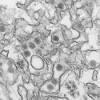

July 21, 2016 10:34 PM. CHICAGO—. As U.S. public health officials try to determine whether Zika has arrived in the country, doctors are establishing guidelines on how to care for the rising number of babies whose mothers were infected with the virus ...

Florida health officials said late Thursday that they are investigating a second case of Zika in a person whose source of infection is unknown.

The state department of Health and Social Services on Friday announced the first known case of the Zika virus in the state. It belonging to a patient treated at the Southeast Alaska Regional Health Consortium's Mt.